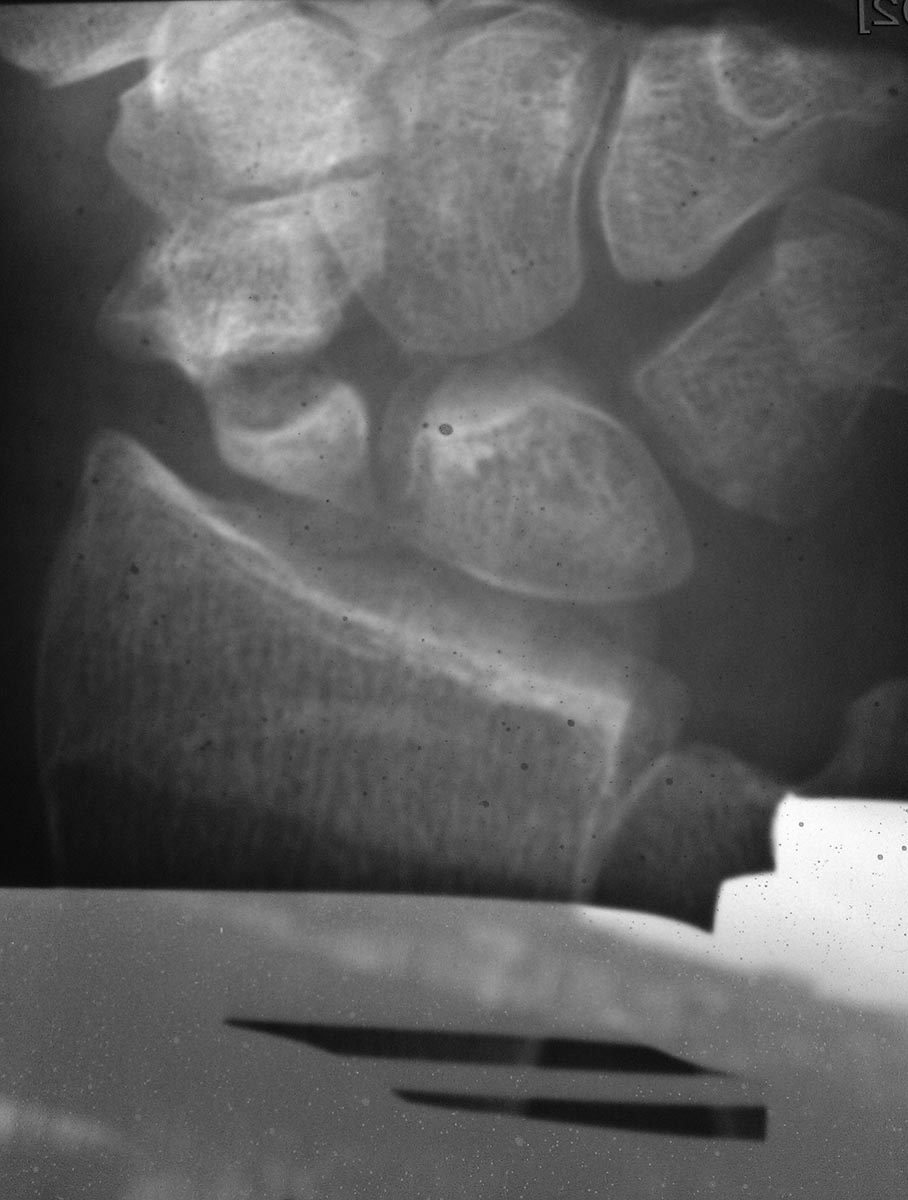

[Ortho] Перелом (ложный сустав?) ладьедидной кости правой кисти

Остальные рентгенограммы сразу не загрузились, попробую ещё раз. А

негатоскопа у нас в ординаторской к большому сожалению нет, поэтому

приходится довольствоваться естественным светом.